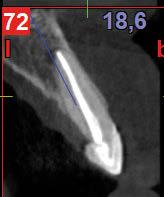

–Implante inmediato en incisivo lateral superior con técnica de «Socket Shield» y acceso vestibular para legrado de la lesión periapical, por el Dr. Ignacio Tormo Jiménez y cols. [106]